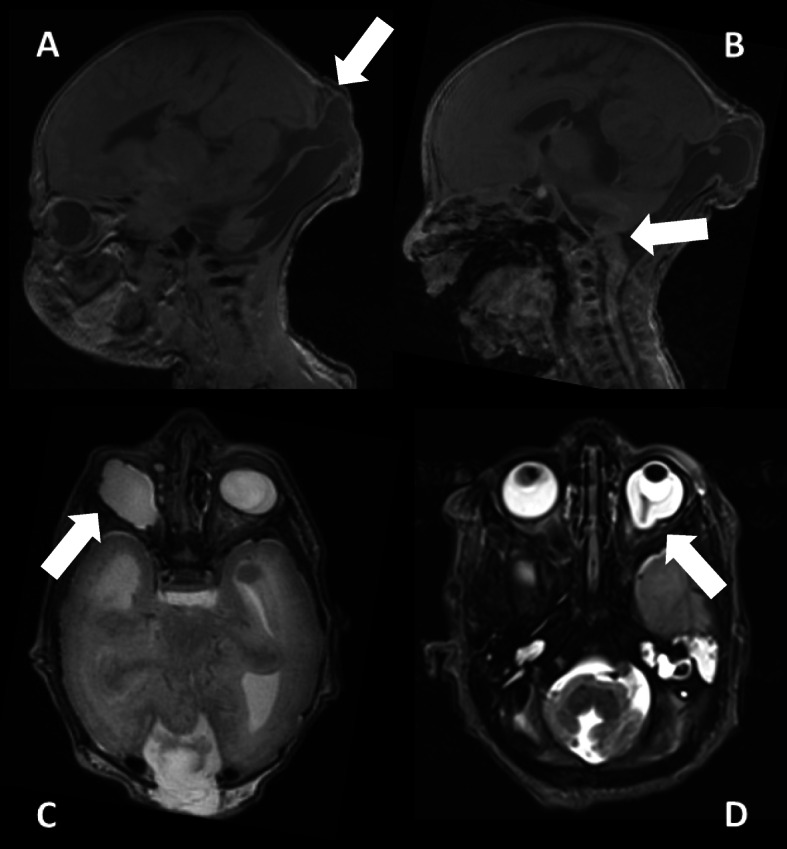

Fig. 6.

Postnatal cranial MRI scan (performed at 2nd / 3rd day); clinical findings: occipital meningocele with dorsal enlarged 4th ventricle (white arrow picture a), vermis hypo−/aplasia (white arrow picture b), generalized polymicrogyria-like cobblestone malformation, temporo-occipital subcortical band heterotopia, eye malformations (G1: microphthalmia with coloboma and caudal cyst, G2: persistent hypoplastic primary vitreous body and posterior staphyloma). a/c = G1, b/d = G2